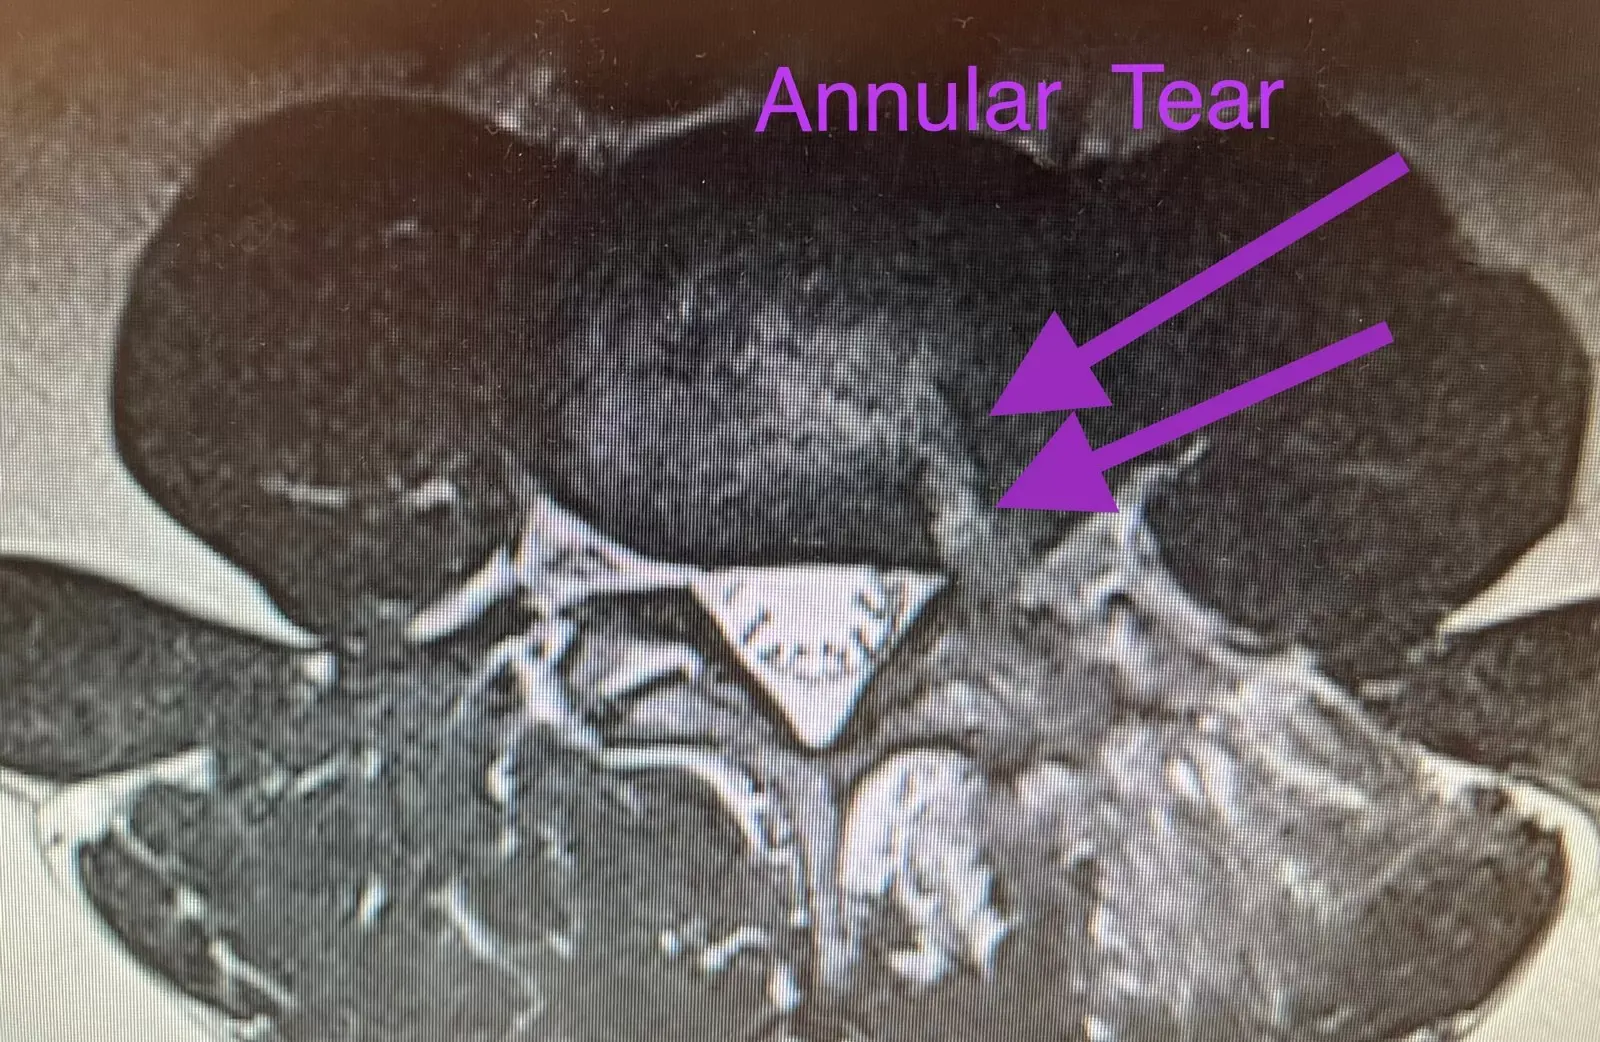

An annular tear develops when the annulus fibrosus, the firm outer tissue of a spinal disc, is damaged and splits open. The jelly-like inner core of the disc, known as the nucleus pulposus, squeezes out of the annular tear and into the spinal canal. It is quite common for an annular tear to be the first insult to a disc that results in a bulging disc. Bulging discs are herniated discs with small herniations of the nucleus pulposus. Through repetitive trauma to the disc, herniations get larger and frequently more symptomatic. Symptoms include back or neck pain, pain down the arm or leg, numbness, tingling and weakness.

An annular tear usually develops from trauma to the intervertebral disc. In its early stages, the tear may not cause any discomfort because the tissue still provides enough support to contain the nucleus pulposus in a painless state. However, as the crack opens wider, the disc’s gel-like central fluid may squeeze out (herniate) under increased pressure from normal activities like bending, jumping, lifting or twisting. This condition can cause high levels of pain and discomfort as we will discuss below.